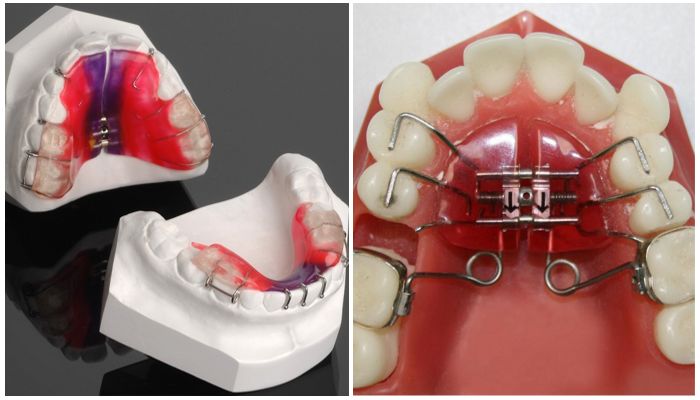

В стоматологии для эстетической коррекции прикуса и выравнивания зубного ряда используется несколько видов надкусочных пломб. Чаще устанавливаются одиночные конструкции на жевательные зубы. При необходимости используются пластины, которые позволяют не только регулировать контакт жевательных зубов нижней и верхней челюсти, но также влияют на положение резцов. Они состоят из металлических и пластиковых элементов.

• Модель Катца. Применяется при сильном выпячивании верхней челюсти (прогнатии). Представляет собой небную пластину, которая изготовлена из пластика. Позволяет мягко исправить дефект верхней челюсти.

• Система Хургиной. Предполагает использование пластины, которая крепится к резцам, а регулируется натяжением винта. Еженедельно корректируется давление на нижнюю часть зубов, в результате чего резцы возвращаются в нормальное положение.